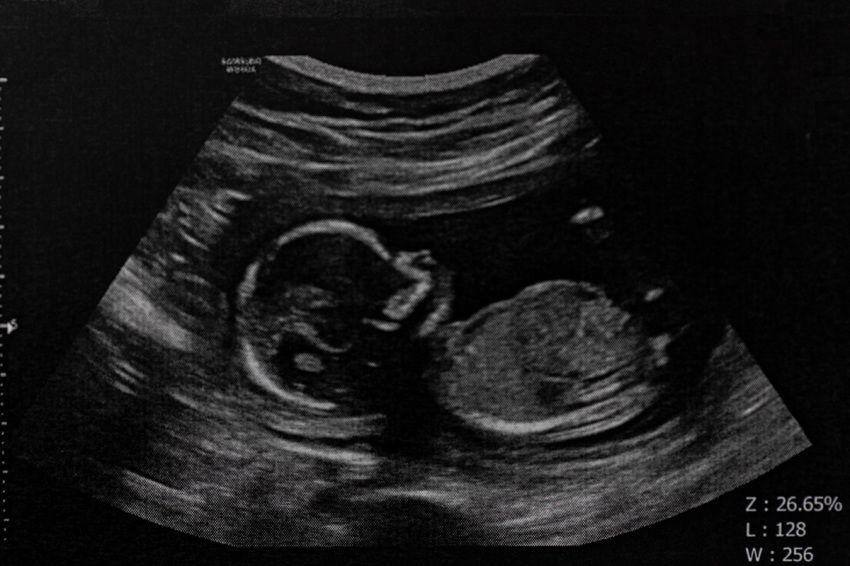

The plaintiff went to an emergency room in Indianapolis, where the remains of “half of a deceased pre-born human being” were found in her right pelvis. The fetal remains were removed and “pieces of the fetal skull that were adherent to the patient’s intestine were removed piecemeal.”